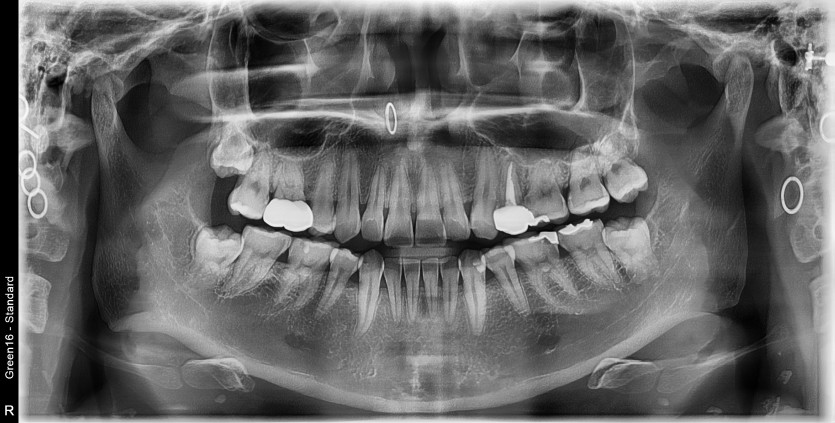

#28,38,48 사랑니 발치

구강 외과 전문의가 당일 발치했습니다.